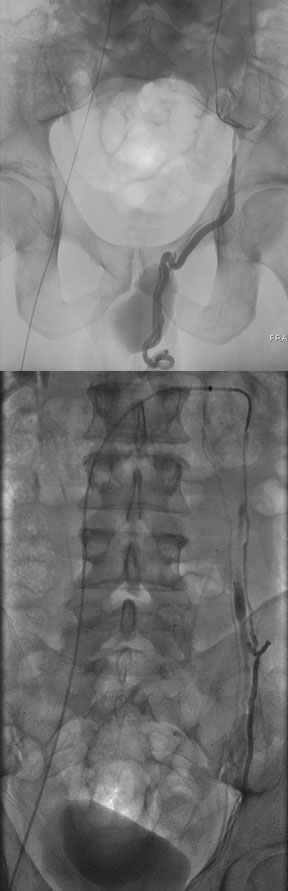

Male varicocele embolization

Left gonadal venogram demonstrates a large left varicocele and two parallel collateral veins that were embolized to complete vascular stasis using hot iodinated contrast and gelfoam. The left testicular pain and swelling have remained resolved for 6 years.